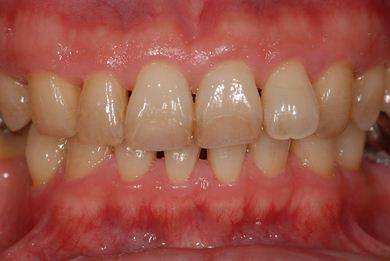

| 性別/年齢 | 男性 / 37歳 | ||||||||||||||||||||||||||||||||

| 主訴 | 前歯(2本)の欠けの治療 | ||||||||||||||||||||||||||||||||

| 治療方針 | 右下欠損部分をインプラント治療にて、機能的・審美的回復を行う。 | ||||||||||||||||||||||||||||||||

| 治療内容 | インプラント1本、メタルボンドセラミッククラウン1本 | ||||||||||||||||||||||||||||||||

| 総治療費 | 252,000円 | ||||||||||||||||||||||||||||||||

| 治療期間 | 7ヶ月 |